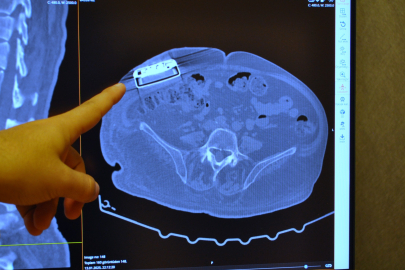

Geçirdiği trafik kazası sonucunda omuriliğinde hasar oluşan ve yaklaşık 11 sene önce kendisine baklofen pompası implante edilen 65 yaşındaki erkek hasta, cihazın değiştirilmesi için Acıbadem Eskişehir Hastanesi müracaat etti. Beyin ve Sinir Cerrahı Uzmanı Dr. Beşir Sürme tarafından hastaya pompa değişimi ameliyatı yapıldı. Operasyon sonucunda, hastaya gelişmiş yeni teknoloji baklofen pompası yerleştirildi. Baklofen pompalarının kullanımının çok yeni olmasa da, bahse konu olan yeni teknolojinin ülkemizde ilk kez kullanıldığı belirtildi.

Operasyonla ilgili açıklamalarda bulunan Beyin ve Sinir Cerrahı Dr. Beşir Sürme, "65 yaşında erkek hasta, trafik kazasına bağlı bir omurilik hasarı geçiriyor ve bunun akabinde parapleji dediğimiz güç kaybı meydana geliyor. Gelişen bu omurilik hasarına bağlı hastada spastisite dediğimiz şiddetli kasılmalar oluşuyor ve hastaya baklofen pompası denilen bir cihaz implante ediliyor. Yaklaşık 11 sene önce implante edilen bu pompanın miadının dolması üzerine bize başvurdu ve biz bu hastamızda bir pompa değişimi ameliyatı gerçekleştirdik. Baklofen pompası tedavisi Türkiye'de daha önce de yapılan bir tedavi ancak biz yeni versiyon bir pompa yerleştirdik ve yeni özellikleri nedeniyle hastaya sağladığı özellikleri de gözlemledik" dedi.

Pompa tedavisinin daha önce uygulandığını ancak yeni teknoloji pompayı ilk kez erkek hastada kullandıklarını söyleyen Dr. Sürme, "Hastamızı yaklaşık 2 ay önce ameliyat ettik. Ameliyat sonrası programlamalarını yaptık. Bu hastalarda, hastalığın durumu ve hastanın ihtiyaçlarına göre verilecek ilacı pompa sayesinde programlayabiliyoruz. Programlamalardan sonra hastamız daha iyi olduğunu ve kasılmalarında belirgin düzelmeler olduğunu söylüyor. Hatta daha önceki pompaya göre şu an daha düşük doz ilaç vermemize rağmen hasta yine bundan fayda görebiliyor" şeklinde konuştu.